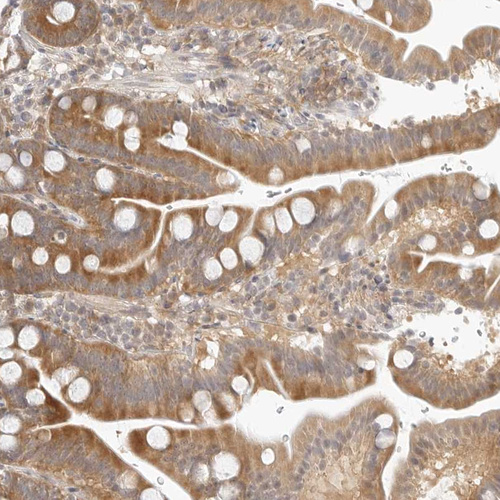

Immunohistochemical staining of human testis shows moderate cytoplasmic positivity in cells in seminiferous ducts and Leydig cells.